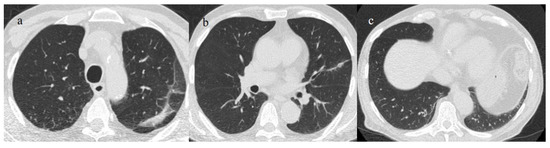

- Melhorn, J.; Achaiah, A.; Conway, F.M.; Thompson, E.M.; Skyllberg, E.W.; Durrant, J.; Hasan, N.A.; Madani, Y.; Naran, P.; Vijayakumar, B.; et al. Pneumomediastinum in COVID-19: A phenotype of severe COVID-19 pneumonitis? The results of the United Kingdom (POETIC) survey. Eur. Respir. J. 2022, 60, 2102522. [Google Scholar] [CrossRef]

- Khaire, N.; Deshmukh, S.; Agarwal, E.; Mahale, N.; Khaladkar, S.; Desai, S.; Kulkarni, A. “Pneumomediastinum: A marker of severity in COVID-19 disease”. Heliyon 2023, 9, e12981. [Google Scholar] [CrossRef] [PubMed]

- Tetaj, N.; Garotto, G.; Albarello, F.; Mastrobattista, A.; Maritti, M.; Stazi, G.V.; Marini, M.C.; Caravella, I.; Macchione, M.; De Angelis, G.; et al. Incidence of Pneumothorax and Pneumomediastinum in 497 COVID-19 Patients with Moderate–Severe ARDS over a Year of the Pandemic: An Observational Study in an Italian Third Level COVID-19 Hospital. J. Clin. Med. 2021, 10, 5608. [Google Scholar] [CrossRef] [PubMed]

- Kecskes, G.; Szabo, A.; Sutori, D.; Maroti, P.; Marovics, G.; Molnar, T.F. Pneumothorax/pneumomediastinum and pre-existing lung pathology in ventilated COVID-19 patients: A cohort study. J. Thorac. Dis. 2022, 14, 4733–4740. [Google Scholar] [CrossRef] [PubMed]

- Dubey, R.; Sen, K.K.; Mishra, A. Barotrauma and its complications in COVID-19 patients: A retrospective study at tertiary care hospital of Eastern India. Bull. Natl. Res. Cent. 2022, 46, 1–8. [Google Scholar] [CrossRef] [PubMed]

- Capaccione, K.M.; D’souza, B.; Leb, J.; Luk, L.; Duong, J.; Tsai, W.-Y.; Navot, B.; Dumeer, S.; Mohammed, A.; Salvatore, M.M. Pneumothorax rate in intubated patients with COVID-19. Acute Crit. Care 2021, 36, 81–84. [Google Scholar] [CrossRef]

- McGuinness, G.; Zhan, C.; Rosenberg, N.; Azour, L.; Wickstrom, M.; Mason, D.M.; Thomas, K.M.; Moore, W.H. IncreaIncidence of Barotrauma in Patients with COVID-19 on Invasive Mechanical Ventilation. Radiology 2020, 297, E252–E262. [Google Scholar] [CrossRef]

- Martinelli, A.W.; Ingle, T.; Newman, J.; Nadeem, I.; Jackson, K.; Lane, N.D.; Melhorn, J.; Davies, H.E.; Rostron, A.J.; Adeni, A.; et al. COVID-19 and pneumothorax: A multicentre retrospective case series. Eur. Respir. J. 2020, 56, 2002697. [Google Scholar] [CrossRef]

- Rodriguez-Arciniega, T.G.; Sierra-Diaz, E.; Flores-Martinez, J.A.; Alvizo-Perez, M.E.; Lopez-Leal, I.N.; Corona-Nakamura, A.L.; Castellanos-Garcia, H.E.; Bravo-Cuellar, A. Frequency and Risk Factors for Spontaneous Pneumomediastinum in COVID-19 Patients. Front. Med. 2021, 8, 662358. [Google Scholar] [CrossRef]

- Zantah, M.; Castillo, E.D.; Townsend, R.; Dikengil, F.; Criner, G.J. Pneumothorax in COVID-19 disease- incidence and clinical characteristics. Respir. Res. 2020, 21, 1–9. [Google Scholar] [CrossRef]

- Shahsavarinia, K.; Rahvar, G.; Soleimanpour, H.; Saadati, M.; Vahedi, L.; Mahmoodpoor, A. Spontaneous pneumomediastinum, pneumothorax and subcutaneous emphysema in critically ill COVID-19 patients: A systematic review. Pak. J. Med. Sci. 2022, 38, 730–735. [Google Scholar] [CrossRef]

- Hamouri, S.; AlQudah, M.; Albawaih, O.; Al-Zoubi, N.; Syaj, S. Spontaneous pneumothorax, pneumomediastinum and subcutaneous emphysema in non-ventilated COVID-19 patients. Futur. Sci. OA 2022, 8, FSO771. [Google Scholar] [CrossRef]

- Shaikh, N.; Al Ameri, G.; Shaheen, M.; Abdaljawad, W.I.; Al Wraidat, M.; Al Alawi, A.A.S.; Ali, H.S.; Mohamed, A.S.; Daeri, H.; Khatib, M.Y.; et al. Spontaneous pneumomediastinum and pneumothorax in COVID-19 patients: A tertiary care experience. Health Sci. Rep. 2021, 4, e339. [Google Scholar] [CrossRef]

- Gandolfo, C.; Bonfiglio, M.; Spinetto, G.; Ferraioli, G.; Barlascini, C.; Nicolini, A.; Solidoro, P. Pneumomediastinum associated with severe pneumonia related to COVID-19: Diagnosis and management. Minerva Medica 2022, 112, 779–785. [Google Scholar] [CrossRef]

- Espinosa, C.; Morente, L.M.; Mansour, E.H.; Yousefzadeh, M.L.; Muzaffarr, Z.M.; Salguero, D.; Vianna, S.D.; Quesada, L.D.; Poli, S.; Garcia, H. Predictors of Spontaneous Pneumomediastinum in Patients with COVID-19 and Ards on High-Flow Nasal Cannula. Chest 2022, 162, A1360–A1361. [Google Scholar] [CrossRef]

- Coppola, M.G.; Lugarà, M.; Tamburrini, S.; Madonna, P.; Panico, C.; Noschese, G.; Pone, E. Pneumomediastinum and Pneumothorax as Relevant Complications of Sub-Intensive Care of Patients with COVID-19: Description of a Case Series. Medicina 2021, 57, 919. [Google Scholar] [CrossRef]

- Palumbo, D.; Campochiaro, C.; Belletti, A.; Marinosci, A.; Dagna, L.; Zangrillo, A.; De Cobelli, F. Pneumothorax/pneumomediastinum in non-intubated COVID-19 patients: Differences between first and second Italian pandemic wave. Eur. J. Intern. Med. 2021, 88, 144–146. [Google Scholar] [CrossRef]